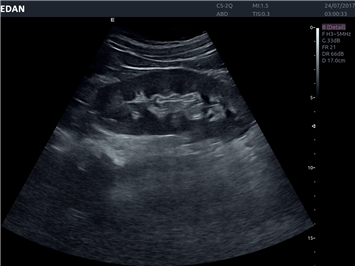

EDAN Acclarix LX4

Расширьте свои представления. Использование усовершенствованной платформой Acclarix система LX4 обеспечивает непревзойденную четкость изображений и интеллектуальный рабочий процесс для всех пользователей, являясь при этом наиболее экономичным решением.

EDAN Acclarix LX4 представляет собой инновационную ультразвуковую систему, построенную на усовершенствованной платформе Acclarix. Сочетание высокого качества визуализации с интеллектуальным рабочим процессом делает эту систему оптимальным выбором для клиник, ценящих эффективность и экономичность.

Система Acclarix LX4 оптимально подходит для:

• Общей визуализации

• Акушерства и гинекологии